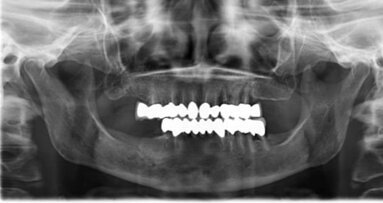

ANN ARBOR, Mich., Stati Uniti d’America – Dentisti e ingegneri biomedici hanno per la prima volta trattato un paziente con un grave difetto parodontale utilizzando uno scaffold polimero bioassorbibile, personalizzato stampato in 3D. Anche dopo il fallimento del sito, 13 mesi dopo la terapia, i ricercatori credono che i biomateriali stampati in 3D possono offrire, in futuro, un’alternativa alle procedure tradizionali per la ricostruzione parodontale.

La procedura è stata eseguita su un paziente di 53 anni di sesso maschile con diagnosi di parodontite aggressiva generalizzata. A causa delle limitate opzioni di ricostruzione, è stato scelto, al fine di preservare la dentatura del paziente, un approccio bioingegneristico che comporta l’impianto di una struttura in 3D per riempire il difetto parodontale, come riferito dai ricercatori.

Secondo il rapporto, è stato utilizzato per il file dati in ingresso il formato STL (STereoLithography) per la produzione dello scaffold più adatto, partendo dalla TAC del difetto. La struttura è stata stampata utilizzando una sinterizzazione laser selettiva con policaprolattone in polvere contenente 4% di idrossiapatite.

I ricercatori hanno raccontato che il sito trattato è rimasto intatto per 12 mesi, a dimostrazione di un guadagno di 3 mm di attacco clinico e della copertura parziale della radice, senza segni di infiammazione cronica o deiscenza. Tuttavia, 13 mesi dopo la terapia, la struttura si è esposta.